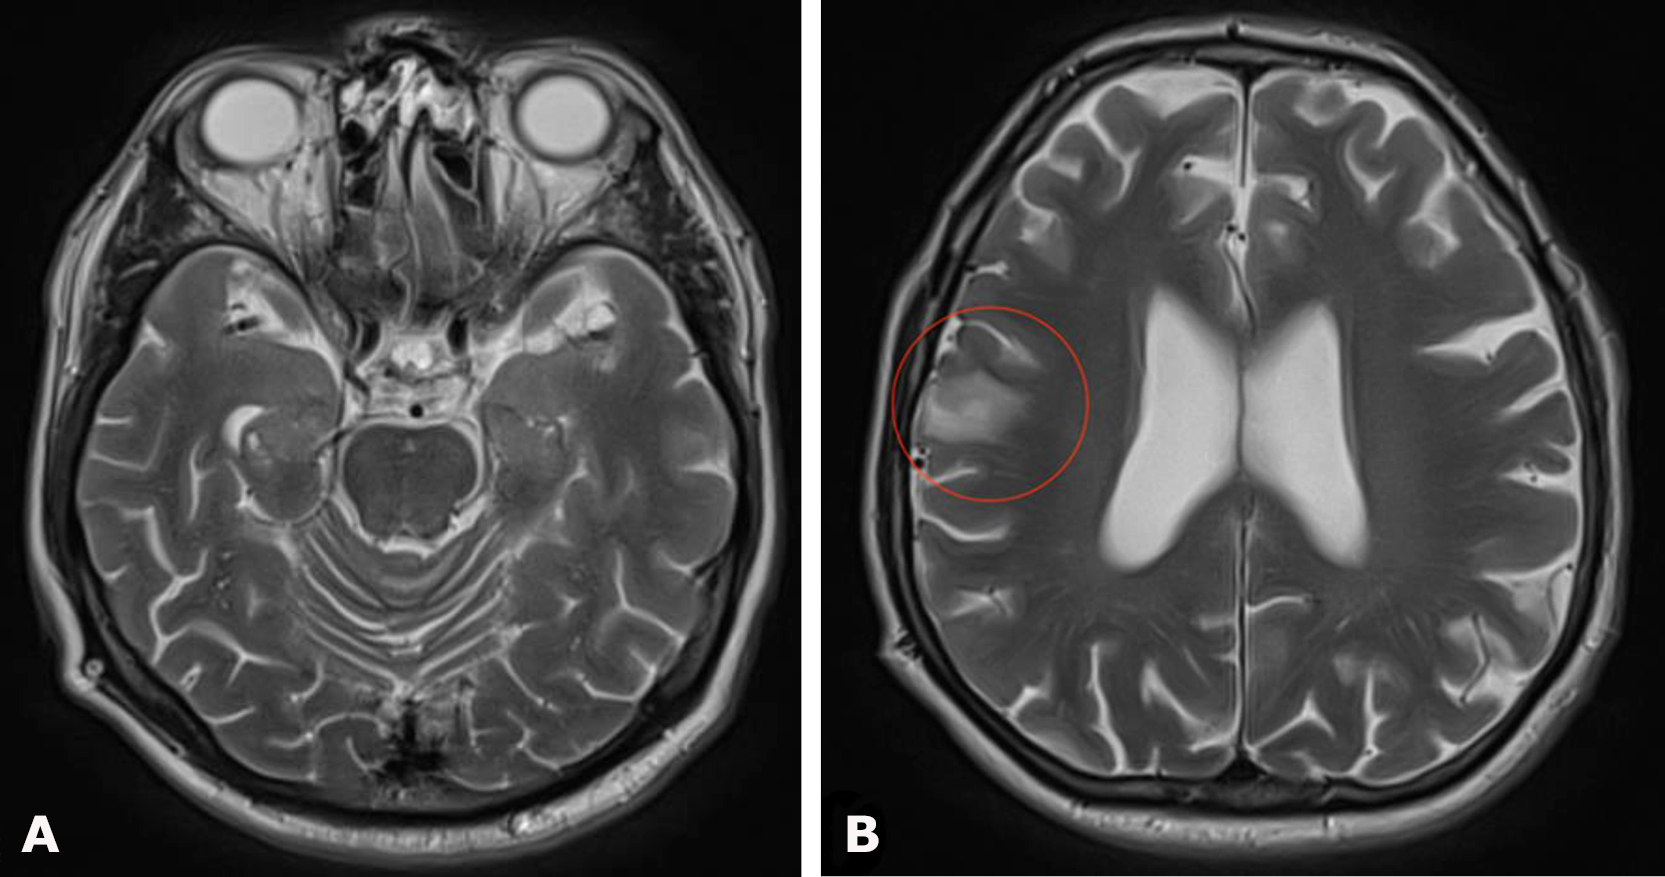

Brain MRI demonstrated a right-sided hemispheric multiloculated cSDH with dimensions (thickness/length/height) of 27/165/87 mm and a 5-mm midline shift to the left (Fig. 10).

Fig. 10. Preoperative brain MRI, T2 FLAIR sequence: A, B – axial projections demonstrating a right-sided hemispheric multiloculated cSDH

Follow-up brain MRI performed 6 months after surgery (Fig. 12) demonstrated complete resolution of the chronic subdural hematoma with restoration of the normal position of the midline brain structures. At follow-up examination, regression of global cerebral symptoms was noted.

Fig. 12. Postoperative brain MRI, T2 FLAIR sequence: A, B – axial projections demonstrating the absence of right-sided chronic subdural hematoma (cSDH)